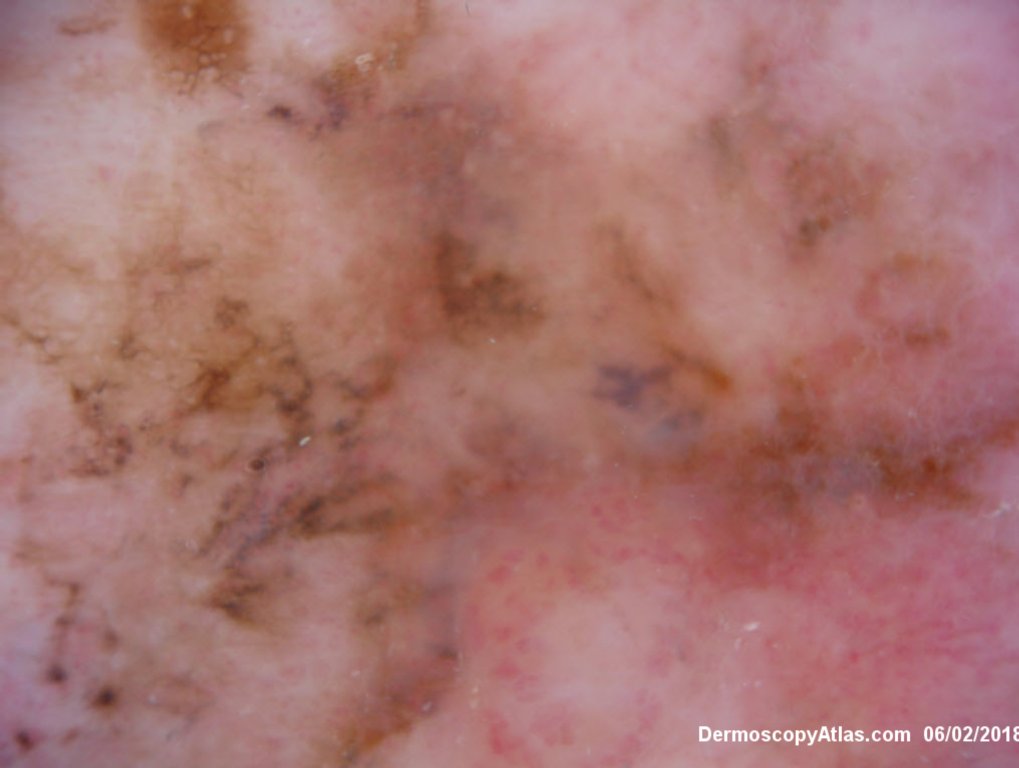

Description: Multiple colours in this pigmented lesion on the lower leg. New pink area

Lady in her early 80s who presented with this lesion on her ankle. The pigmented area had been there for some time but the pink area was bleeding and new. Shave of surrounding area and a punch biopsy of the new pink area showed mainly surrounding in situ melanoma with invasive melanoma in the pink area 1.8 mm thick. Having a 2cms margin excision of the whole area and a graft.